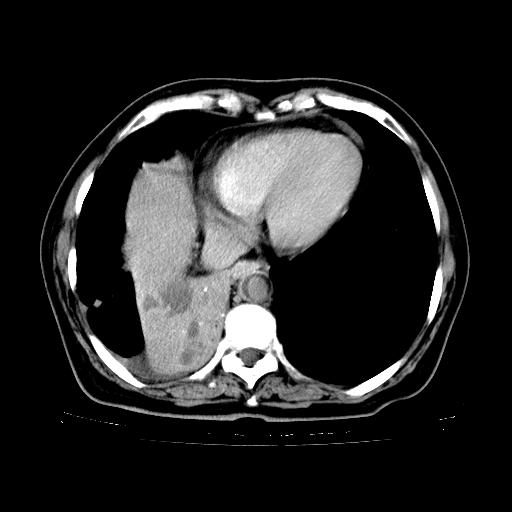

女,70岁,咳嗽、咳痰一个月,低热一周。

1.左上肺结核,部分纤维化。右肺中下叶部分肺不张,内见液化、坏死及点状钙化,右中下叶支气管壁增厚、管腔狭窄,见多个点状钙化,结合临床考虑支气管内膜结核,建议痰检查抗酸杆菌并参考血沉。两肺多个小圆点状高密度灶,境界模糊,多考虑结核肺内播散。但本人年龄较大首先应支气管镜检以除外右肺癌。

2.胸主动脉夹层。